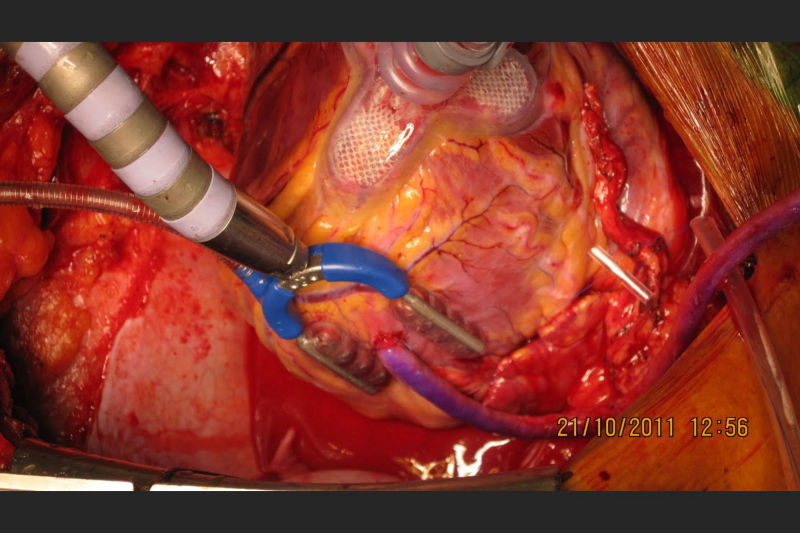

Led Malabar's first successful heart transplantation done at Metromed International Cardiac Centre on a 54 year old patient with end stage heart disease. Donor heart was harvested from a 28 year old gunshot victim in Kannur and brought to MICC through a green corridor. The transplanted patient is healthy and on minimal medication. For end stage cardiac disease, heart transplantation is the gold standard. Post transplant, they have a near normal life.